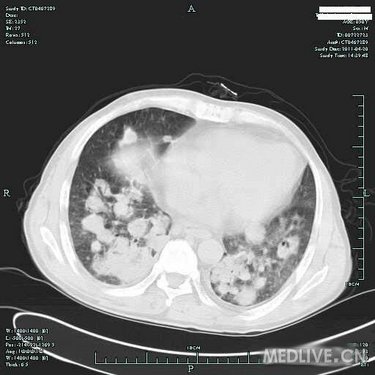

病史特点:患者于3月余前受凉后出现发热,体温为39.0摄氏度左右,伴咳嗽,为阵发性咳嗽,有咳痰,色白,有咽痛,无鼻塞及流涕,至当地诊所输液(具体不详)治疗后,效果不明显。于80天前入住当地医院,住院期间查胸部CT提示:双肺弥漫性结节影,纤支镜:双叶段粘膜轻度充血、水肿,痰找脱落细胞阴性,行左下肺经皮肺穿刺针吸细胞学未见异形细胞,曾予哌拉西林/他唑巴坦针、利福平、氟康唑针等治疗后,仍有反复发热,体温高达39.0摄氏度左右,发热时有气促感,无胸痛、头痛及心悸感。于2月余前至我院住院,CRP41.80mg/L,肺CT增强:两肺多发病灶,肿瘤不能排除,建议穿刺活检;气管镜检查:两侧支气管均通畅,未见新生物,气管镜刷片、肺泡灌洗液均未见肿瘤细胞;进一步行肺穿,肺穿刺涂片找到坏死组织,涂片未见肿瘤细胞,穿刺病理:(右)肺组织慢性炎伴坏死及淋巴组织增生;骨髓活检:造血细胞增生活跃伴散在T细胞浸润。予以出院带药HRE诊断性抗结核+SMZco治疗,患者用药不规则,仍有反复发热,最高达40摄氏度,伴畏寒,予退热药处理后热退,伴少量咳嗽及呕吐,无明显咳痰,复查肺部CT病灶对比前片增多、增大,为进一步诊治收住入院。

T 37.2℃,R 20次/分,P 82次/分,BP 114/79mmHg,神清,精神偏软,浅表淋巴结未及肿大,双肺呼吸音粗,未及明显干湿啰音,心律齐,瓣膜区未闻及病理性杂音,腹平软,无压痛及反跳痛,肝脾肋下未及,双下肢无浮肿,右上肢肌力IV级,握力差。

血常规(五分类)(病房):白细胞计数3.8×10E9/L,中性粒细胞(%) 84.8%,淋巴细胞(%) 4.7%,血红蛋白106g/L,血小板计数279×10E9/L。

血生化:总蛋白50.3g/L,白蛋白27.4g/L,球蛋白22.9g/L,白球蛋白比例1.2。 ANCA,MPO,PR3等检查未见明显异常。 癌胚抗原7.8ng/mL,神经元特异性烯醇化酶44.0。